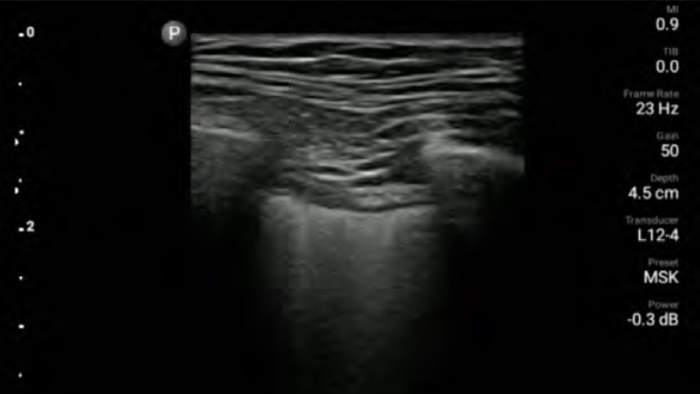

Ультразвук у постели больного

Использование системы Lumify у постели больного может быть ценным инструментом для определения содержимого желудка и снижения риска легочной аспирации. Это может снизить риск осложнений при анестезии.